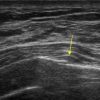

Gãy xương sườn

» Thông tin: Nữ giới – 52 tuổi.

» Lâm sàng: Chấn thương ngực.